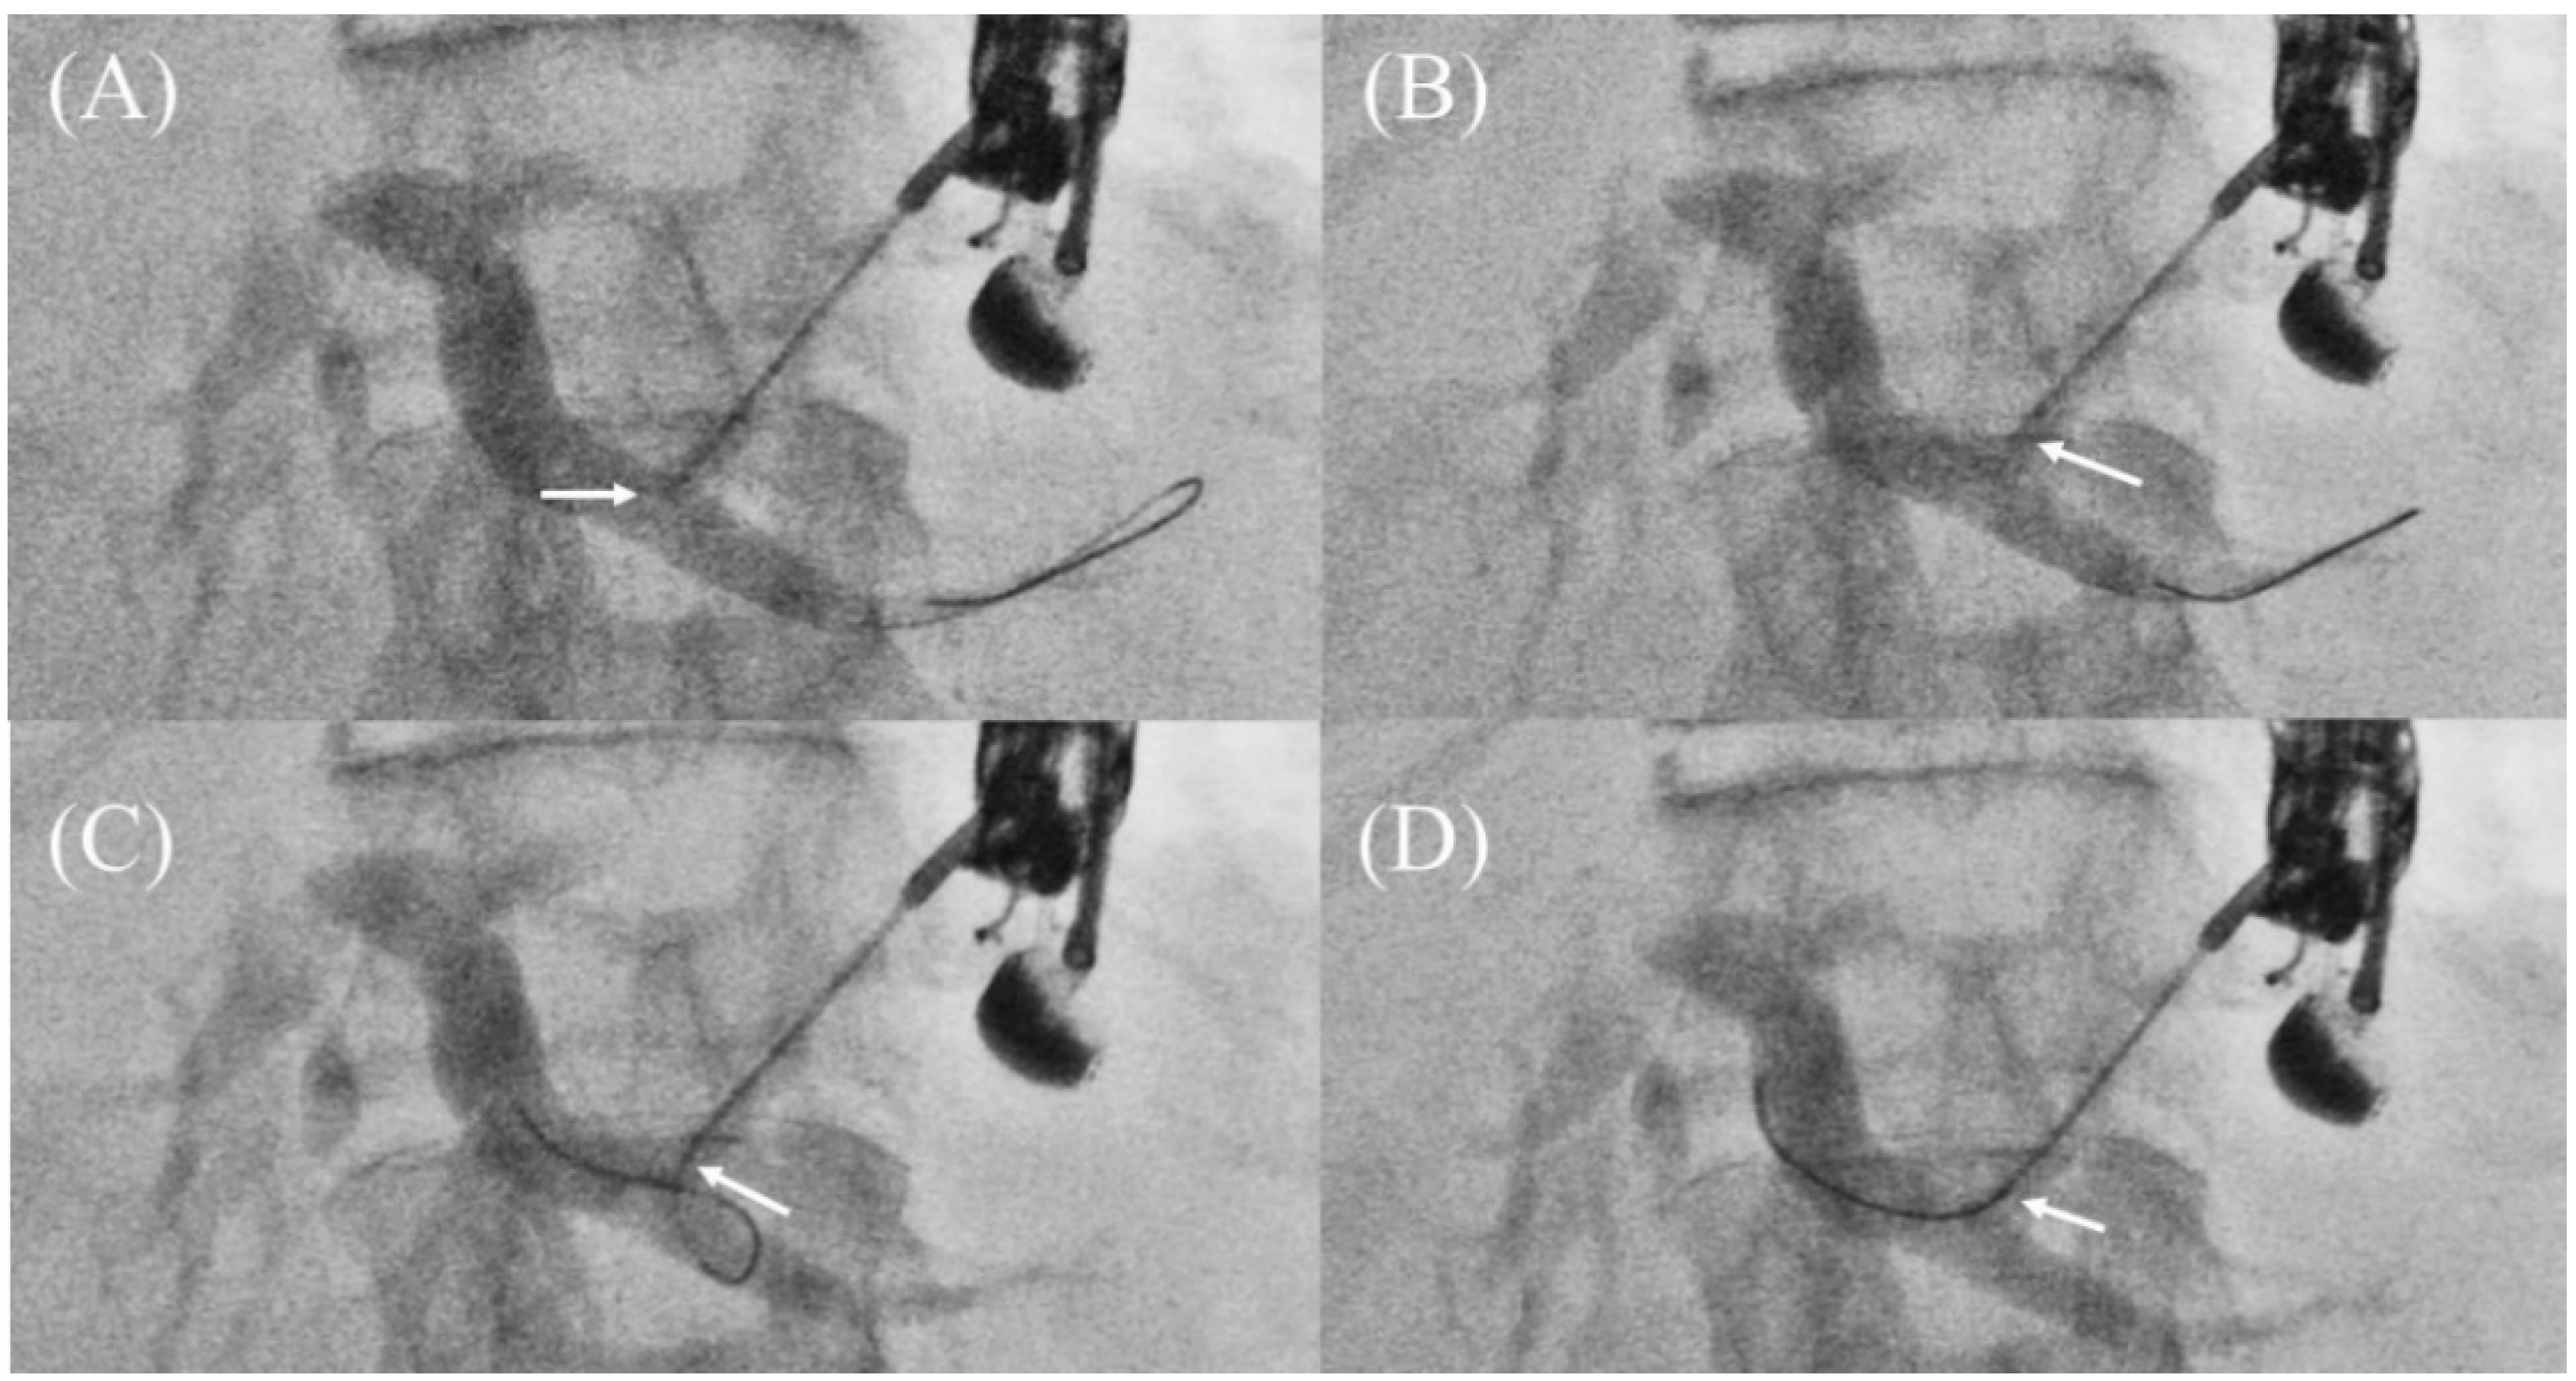

- Ueno, S.; Ogura, T.; Higuchi, K. Moving scope technique for guidewire insertion during endoscopic ultrasound-guided hepaticogastrostomy. Dig. Endosc. 2021, 33, e109–e110. [Google Scholar] [CrossRef]